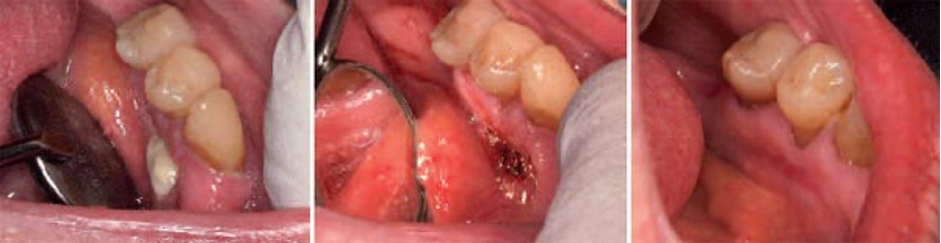

Fig. 32 – 34: Trattamento di terapia parodontologica chiusa: decontaminazione primaria delle tasche e ablazione dei tessuti di granulazione con laser Nd:YAG, poi segue il risciacquo H₂O₂ e curettage combinato con Er:YAG & Varian al quarzo (Fotona). Decontaminazione finale in profondità delle tasche e PBM, entrambi con laser Nd:YAG rispett. a diodi (810nm). Coagulo di sangue come medicazione con l’impiego del laser Nd:YAG a impulsi di lunga durata.

Nella terapia aperta il laser Er:YAG riveste un ruolo principale nel taglio di apertura del lembo, la modellazione dei lembi interni ed esterni, la rimozione dei tessuti di granulazione e dei concrementi, la pulizia delle superfici radicali infette e la de-epitelializzazione finale, con il supporto di un’ulteriore fotobiomodulazione col diodo 810nm.

Fig. 35 – 37: Fasi della terapia parodontologica aperta: dopo l’apertura e un’iniziale rimozione del tessuto inclusa la deepitelializzazione finale e sutura. La fotobiomodulazione con il diodo 810 omunque fa sempre parte della chirurgia.